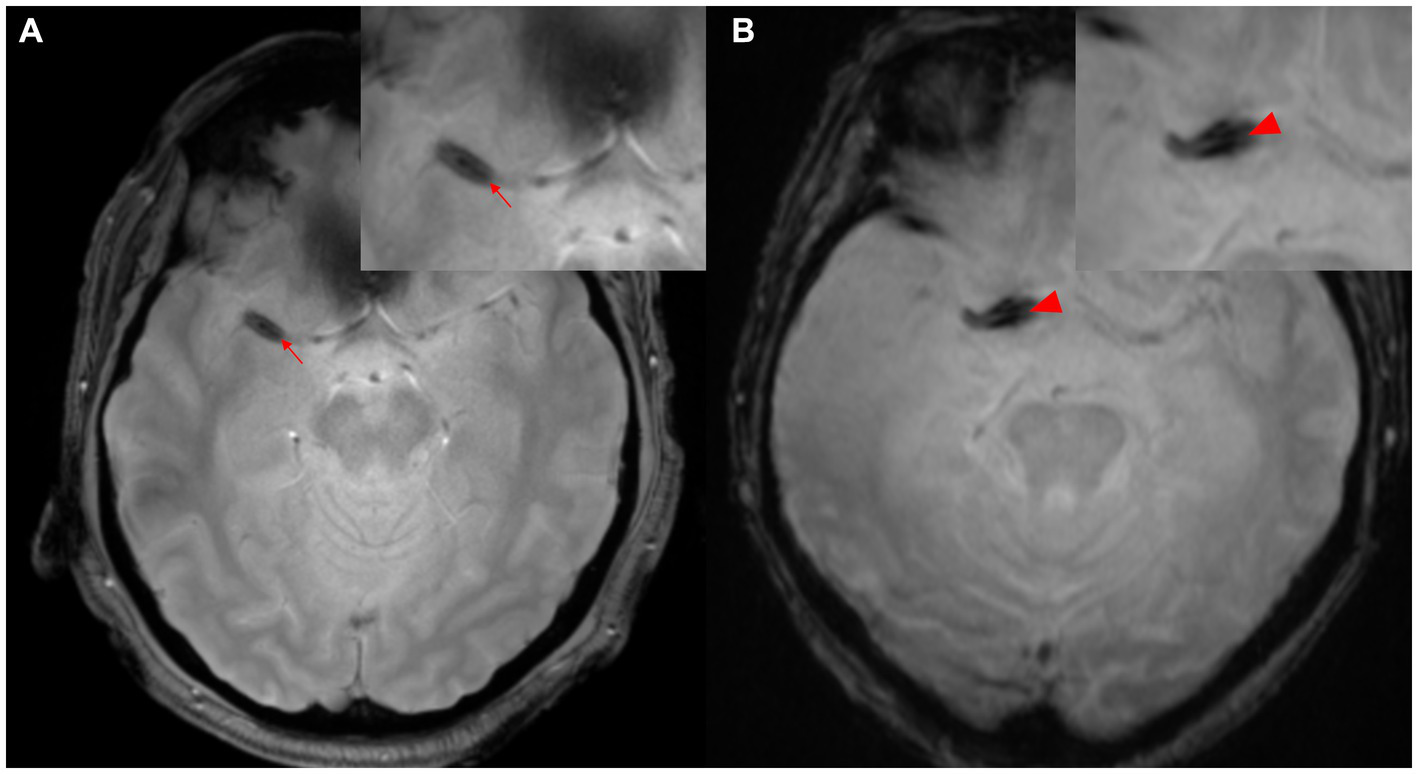

2.2. Susceptibility vessel sign/2-layered susceptibility vessel sign

The concept of SVS has been classically defined as “a manifestation of low signal intensity in occluded thrombi on T2*-weighted Gradient Echo (GRE) images, caused by the magnetic susceptibility effect of deoxyhemoglobin in red blood cells” (14). The diagnostic value of SVS in ischemic stroke is widely acknowledged, with a prevalence of 77.5% in cases of cardioembolism (15). This is particularly evident in thrombi with high concentrations of red blood cells (known as “red thrombi”) (16). Moreover, the presence of GRE-SVS has been associated with cardioembolism and spontaneous recanalization of occluded vessels (17, 18). The diameter of SVS has been independently linked to the likelihood of cardioembolism (adjusted odds ratio [OR], 1.97; 95% confidence interval [CI], 1.34–2.90; p < 0.01). However, it is important to note that a diagnosis of SVS does not necessarily indicate cardioembolism, as 25.5% of patients without cardioembolism also exhibit SVS (14). In cases of the middle cerebral artery (MCA) diagnosed via cerebral angiography, the sensitivity of SVS was higher than that of the hyperdense MCA sign NCCT (82% vs. 54%) (14). The concept of “2-layer SVS” (as shown in Figure 2) on 3-T MR T2*-weighted GRE has been reported in Japan, where 47.7% of 132 patients (72 men, mean age 74.5 years) were diagnosed with cardioembolism. The sensitivity of SVS for cardioembolism and large-artery atherosclerosis was not statistically significant (74.6% vs. 58.0%), but the sensitivity of 2-layer SVS alone was found to be significantly higher for cardioembolism (42.9%) than for large-artery atherosclerosis (2.9%; p < 0.001) (19). The specificity of 2-layer SVS for cardioembolism and the diagnostic ratios were 97.1 and 25.1%, respectively (42.0 and 2.1% for SVS). These findings may be attributed to the magnetic heterogeneity within the thrombus, suggesting a significant correlation between 2-layer SVS and higher thrombus weight and red blood cell components (19–21).

Figure 2

Two-layer SVS. (A) SVS (arrowhead) is seen distal to M1 of the right MCA. (B) SVS (arrowhead) is seen in the right internal carotid artery proximal to M1 segment of MCA. MCA, middle cerebral artery; SVS, susceptibility vessel sign.